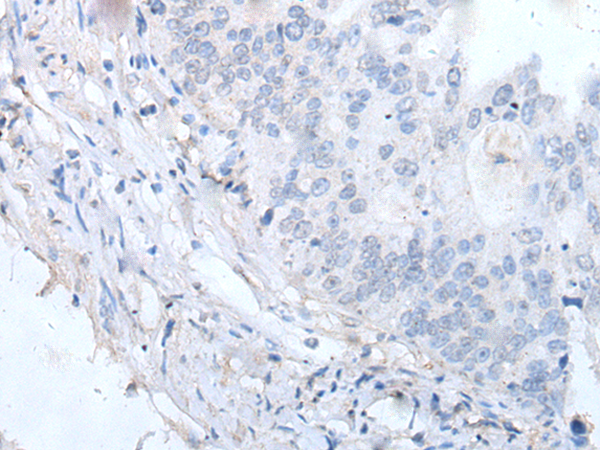

IHC positive control: |

Human colorectal cancer and human tonsil |

IHC Recommend dilution: |

20-100 |